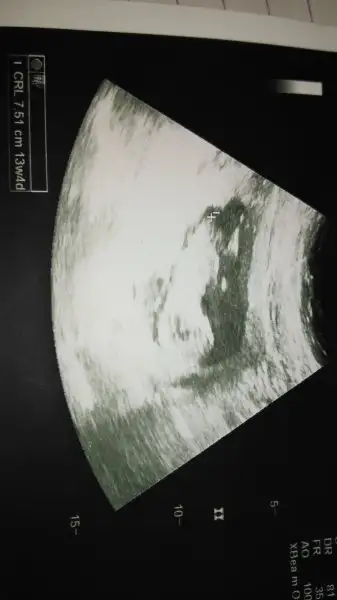

Hayırl geceler ilk defa bu sayfayı takip etmeye başladım.Bana da yardımcı olsbilirmisiniz cinsiyetini öğrenmedik daha bilen arkadaşlar yardımcı olursanız cok mutlu olurum.13+4